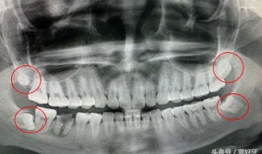

• 拔智齿视频全真实过程,拔智齿的真实手术过程

你知道吗?拔智齿这个话题,最近在网络上可是火得一塌糊涂呢!很多人都在好奇,拔智齿到底是个啥样的过程,是不是像传说中的那么恐怖?今...